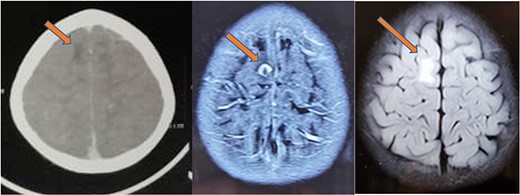

The histopathology report revealed the presence of a parasite composed of cuticle, subcuticular cells along with muscle, and chronic inflammatory infiltrate with a final impression of cysticercosis (Fig. 5). After this diagnosis, we reevaluated our history with more details. There was no history of headaches, seizures, or visual difficulties. The patient was found to be a vegetarian in diet. A pediatric physician evaluation was also done where a contrast-enhanced computed tomography (CECT) brain and ophthalmic examination were advised to evaluate for a possibility of neurocysticercosis. The ophthalmic examination was within normal limits, but the CECT showed a hypodense area in the right frontal lobe (Fig. 6). On further correlation with contrast MRI, a ring-enhancing lesion in the right paramedian frontal lobe surrounded by non-enhancing vasogenic edema was seen. Another small lesion was seen in the right external capsule surrounded by minimal edema (Fig. 6). Both lesions appeared to be granulomatous, giving an impression of neurocysticercosis. The child was treated with syrup albendazole 15 mg/kg per day in two divided doses for 1 month. A short course cover of dexamethasone 0.1 mg/kg per day started 1 day before albendazole was started, continued for a month, and then tapered over a week.

CT (left) showing a hypodense lesion in the right frontal lobe, T1 post-contrast MRI image (center) showing a ring enhancing lesion in the right frontal lobe and FLAIR image (right) showing non-enhancing vasogenic edema surrounding the lesion.